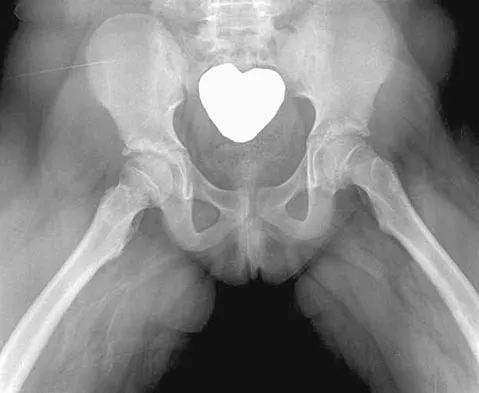

Figure 11 shows the radiograph of a 26-year-old man with type I diabetes mellitus who was struck by a motor vehicle. What is the most common complication associated with this pelvic fracture?

Explanation

The most common complication following acetabular or pelvic ring injury is deep venous thrombosis (DVT). Without prophylaxis, rates of DVT are as high as 70% to 80%. With prophylaxis, the rates are around 10%. Infection rates in surgical repair of acetabular fractures are relatively low but a history of diabetes mellitus and a significant Morel-Lavalle lesion certainly increase the risk. However, even with these two complicating factors, the rates of infection are still lower than 10%. Sciatic nerve palsy rates from the injury alone approach 20% and iatrogenic injury is usually less than 2%. Degenerative changes to the hip following this injury approach 20% to 25%, even with an anatomic reduction. Geerts WH, Code KI, Jay RM, et al: A prospective study of venous thromboembolism after major trauma. N Engl J Med 1994;331:1601-1606.